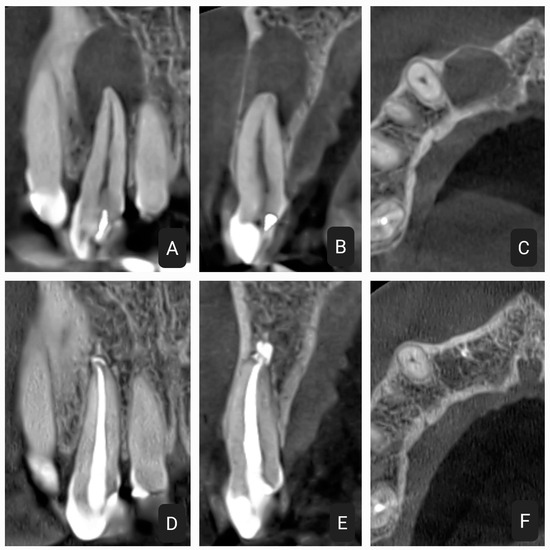

2.1. First Case

2.2. Second Case

2.3. Third Case

2.4. Fourth Case

2.5. Fifth Case

2.6. Control Periapical X-rays